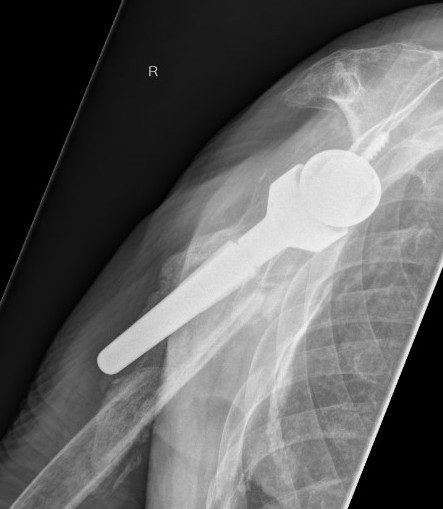

Reverse TSR OvertighteningReverse TSR Overtightening 2

Overlengthened arm post rTSA